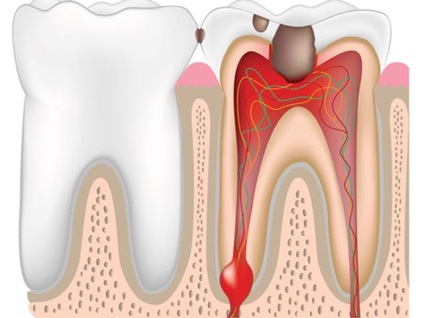

- Gyökérzetet. vagy gyökérzetet ciszta - a leggyakoribb betegség kialakulásához. Daganatok miatt előforduló nem megfelelő fogászati kezelés, vagy a periodontális szöveti gyulladást. Fejleszti a sűrű, gyulladt csomók a gyökere a fog. Ezek a ciszták vannak kialakítva az arcüreg és eléri átmérője 2 cm. Bent a nem szarusodott epiteliális neoplazma bélelt ruhával bevont cisztafalat immunsejtek és a plazma. A válság a betegség vezet gyulladásos folyamat: a sejtek fokozott mennyisége és hajtásképződést formájában szálak, befelé irányuló fal. Ezek a tünetek csak akkor fordul elő ebben a formában a betegség.

ciszta gyökér

Működés menteni a fogat - eltávolítását a gyökércsúcs. Fogak, amelyek a ciszta üregében a műtét után csökken, ezért menteni őket értelmetlen. Fogak komplex szerkezete a gyökérzet gyakran van kitéve eltávolítását, amely által okozott dolgoztak áthaladását gyökércsatornák. A műtét során eltávolított fogát, ha azok a kiváltó oka a ciszták. Erre a célra elektroodontometriya. Ha a fog nem reagál az elektromos áram és a röntgen vizsgálat nem mutatott bővítése periodontális térben, fogorvos lezárjuk a fogat a műtét előtt.